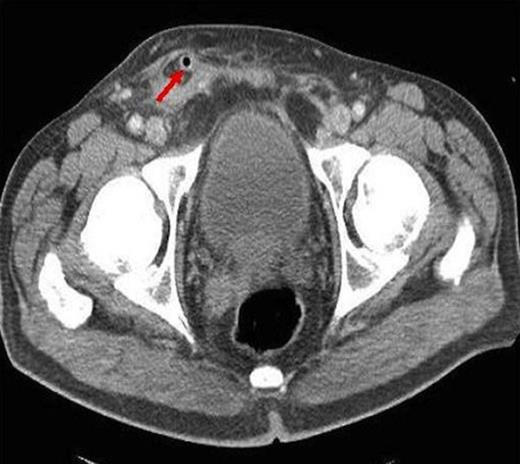

A 61-year old male presented with a 12 hours of right testicular pain, scrotal erythema and raised inflammatory markers (C-Reactive Protein 324 mg/L & leukocytosis 19.9 X 109/L) on background of right inguinal hernia repair 5 years ago and more recent recurring left epididymo-orchitis. He was provisionally diagnosed with right epididymo-orchitis. CT was performed because the pain was extending to the pubic tubercle, previous hernia surgery and markedly raised inflammatory markers. This showed an acutely inflamed appendix within a small recurrent direct inguinal hernia, entering the scrotum with surrounding inflammatory soft tissue (Figure 1, 2).

Axial CT showing luminal air of appendix segment in the scotum (arrow)